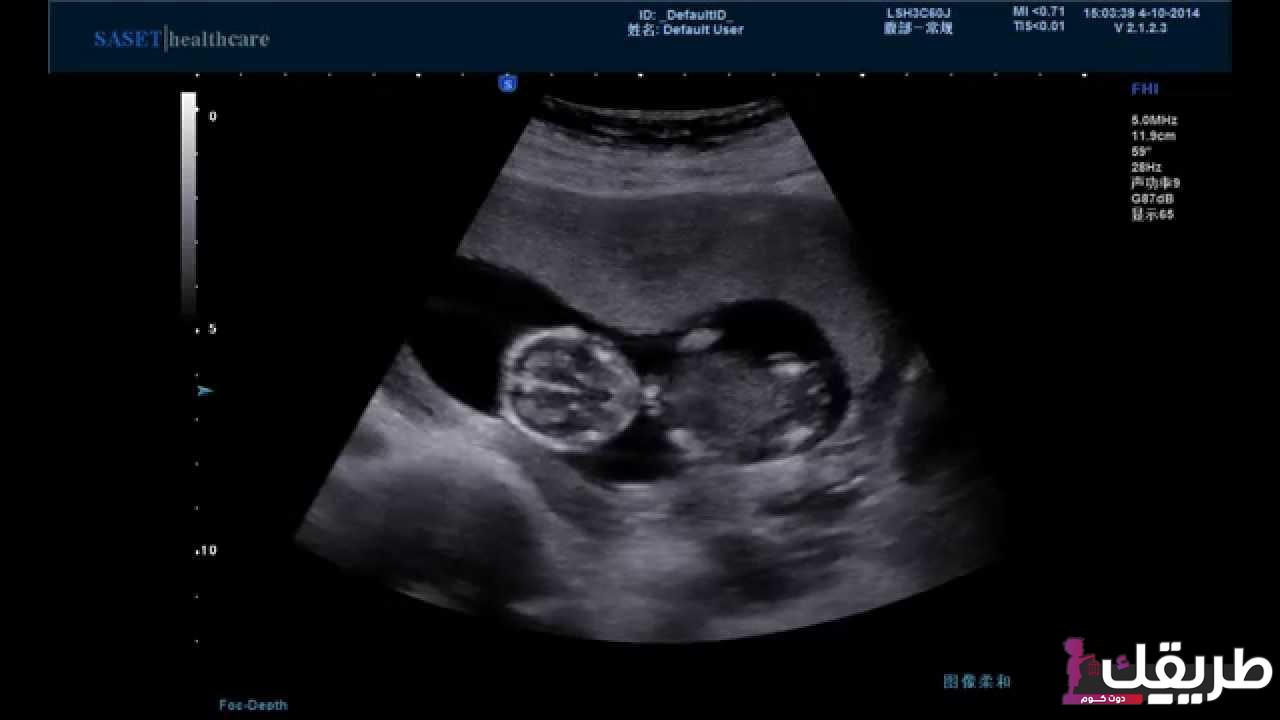

- تبدأ الأم في سماع نبض الجنين.

- تصل نبضات قلب الجنين إلى ١٥٠ نبضة في الدقيقة الواحدة.